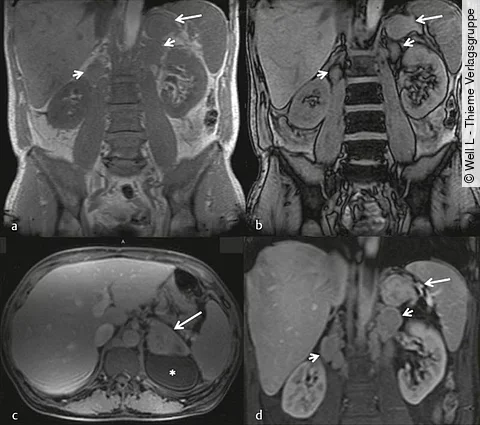

Uro-Quiz der Woche

Auflösung: Hufeisenniere mit weiterer Auffälligkeit

| Auflösung Know-how gefragt!

| News

| Auflösung Know-how gefragt!